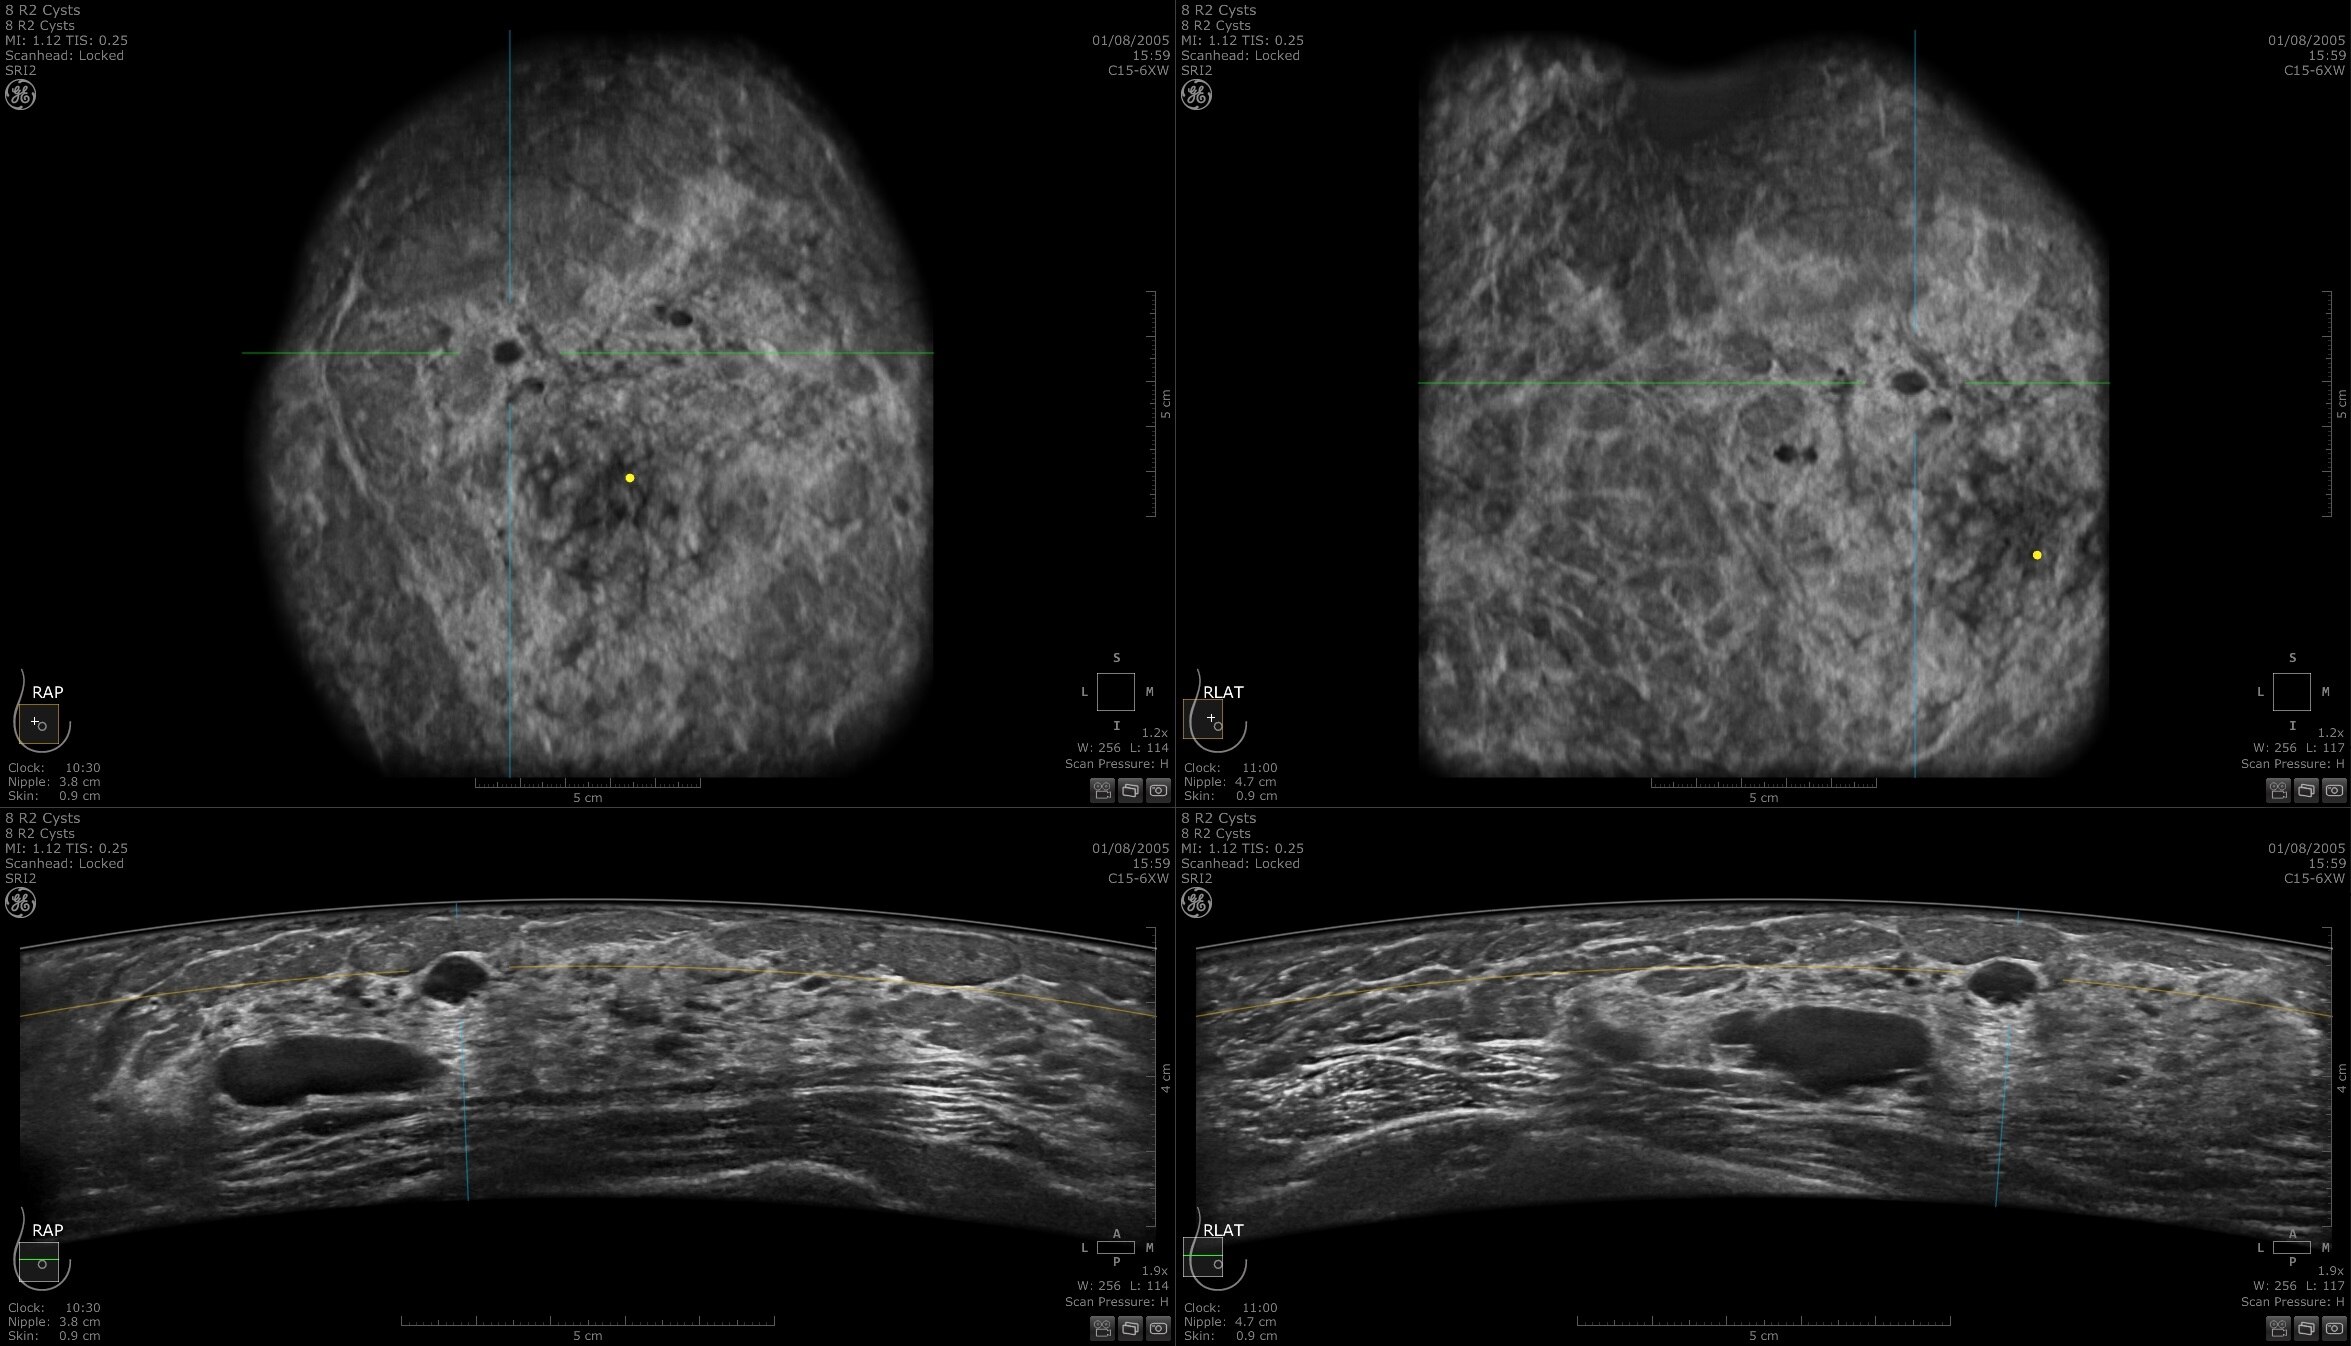

Dense breast tissue and cancer appear white on a mammogram, potentially camouflaging small cancers. Invenia ABUS 2.0, is specifically designed to help clinicians find cancers that may be hidden on mammography1,2.

Lesion characterization for confident staging in dense breasts

Invenia ABUS 2.0 uses the latest ultrasound innovations and AI based solutions to help improve precise diagnosis and elevate clinical confidence.